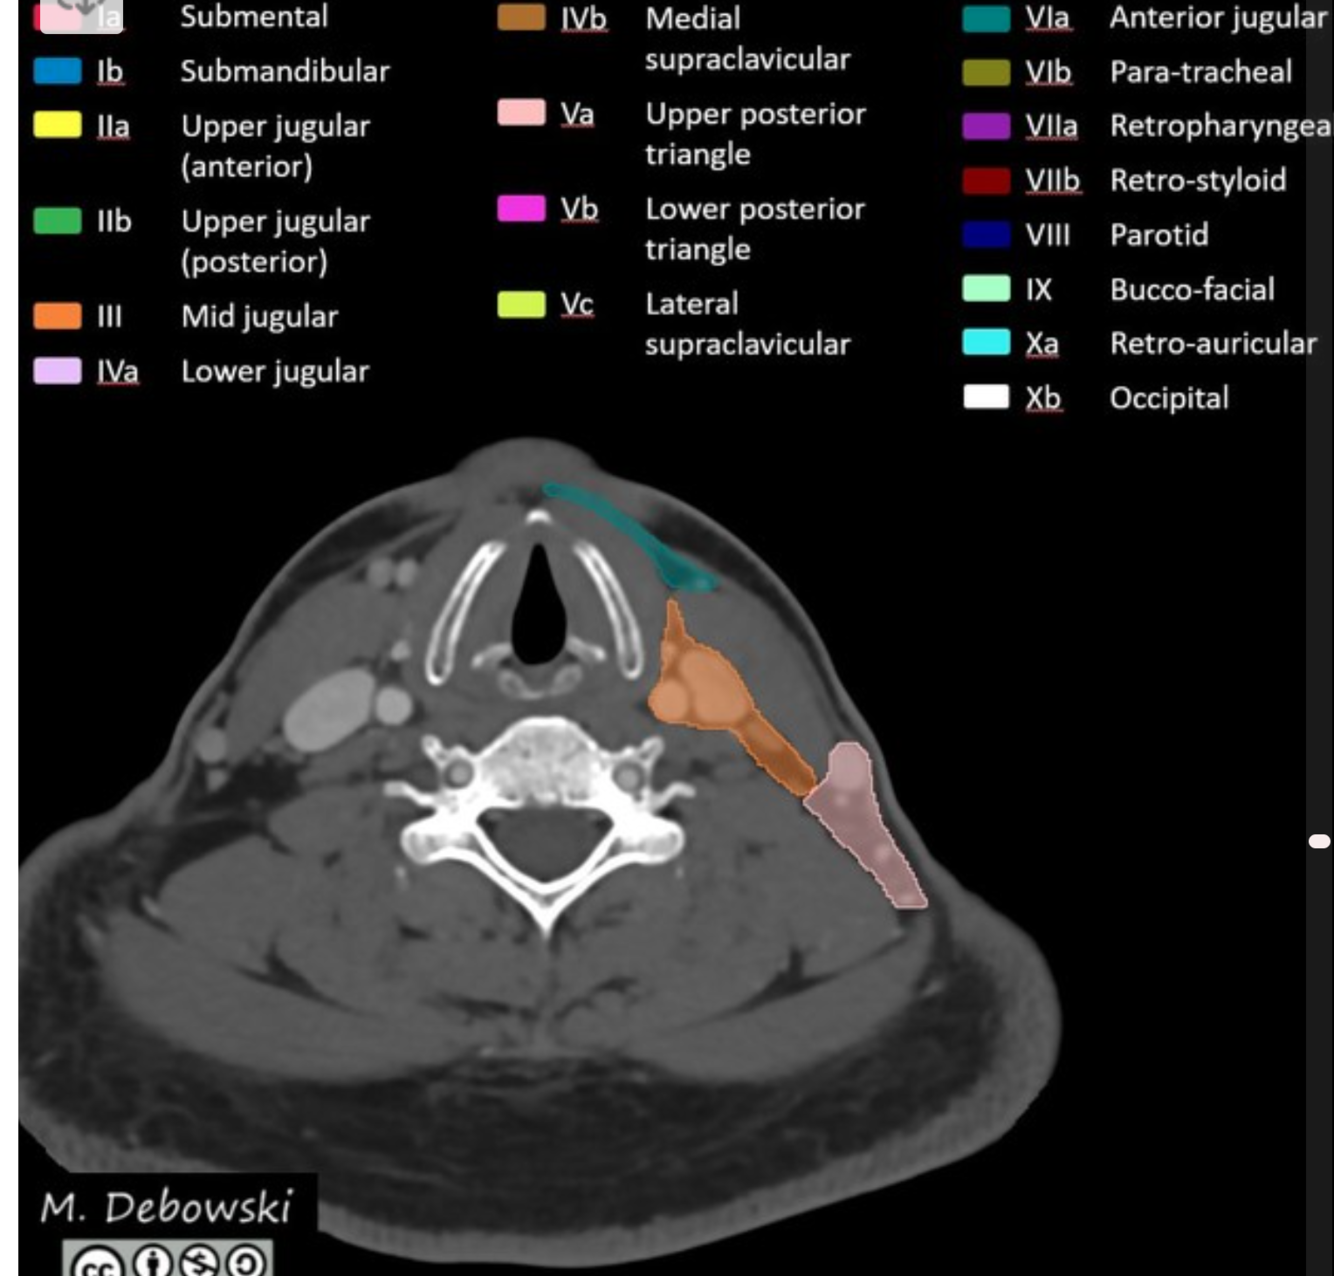

Level II: upper internal jugular (deep cervical) chain

superiorly: base of the skull at the jugular fossa

inferiorly: inferior border of the hyoid bone

anteriorly: posterior border of the submandibular gland

posterolaterally: posterior border of the sternocleidomastoid muscle

medially: medial border of the internal carotid artery

There are two sublevels:

level IIa: inseparable from or anterior to the posterior edge of the internal jugular vein; includes jugulodigastric nodal group

level IIb: posterior to and separable by a fat plane from the internal jugular vein

Level IV: lower internal jugular (deep cervical) chain

superiorly: inferior border of the cricoid cartilage

inferiorly: level of the clavicle/manubrium

anteriorly: anterior border of the sternocleidomastoid muscle

posterolaterally: oblique line drawn through the posterolateral edge of the sternocleidomastoid muscle and the lateral edge of the anterior scalene muscle 2

medially: medial border of the common carotid artery

includes medial supraclavicular nodes including Virchow node 1

Level V: posterior triangle

superiorly: skull base at the apex of the convergence of sternocleidomastoid and trapezius muscles

inferiorly: level of the clavicle

anteromedially: posterior border of the sternocleidomastoid muscle

posterolaterally: anterior border of the trapezius muscle

level Va: superior half, superior to inferior border of the cricoid cartilage (posterior to levels II and III); includes spinal accessory nodes

level Vb: inferior half, inferior to inferior border of the cricoid cartilage (posterior to level IV); includes lateral supraclavicular nodes 1

Level VI: central (anterior) compartment

superiorly: inferior border of hyoid bone

inferiorly: superior border of manubrium (suprasternal notch)

anteriorly: platysma muscle 8

posteriorly: trachea (medially) and prevertebral space (laterally) 8

laterally: medial borders of both common carotid arteries (medial to levels III and IV)

includes anterior jugular, pretracheal, paratracheal, prelaryngeal/precricoid (Delphian), and perithyroidal nodes